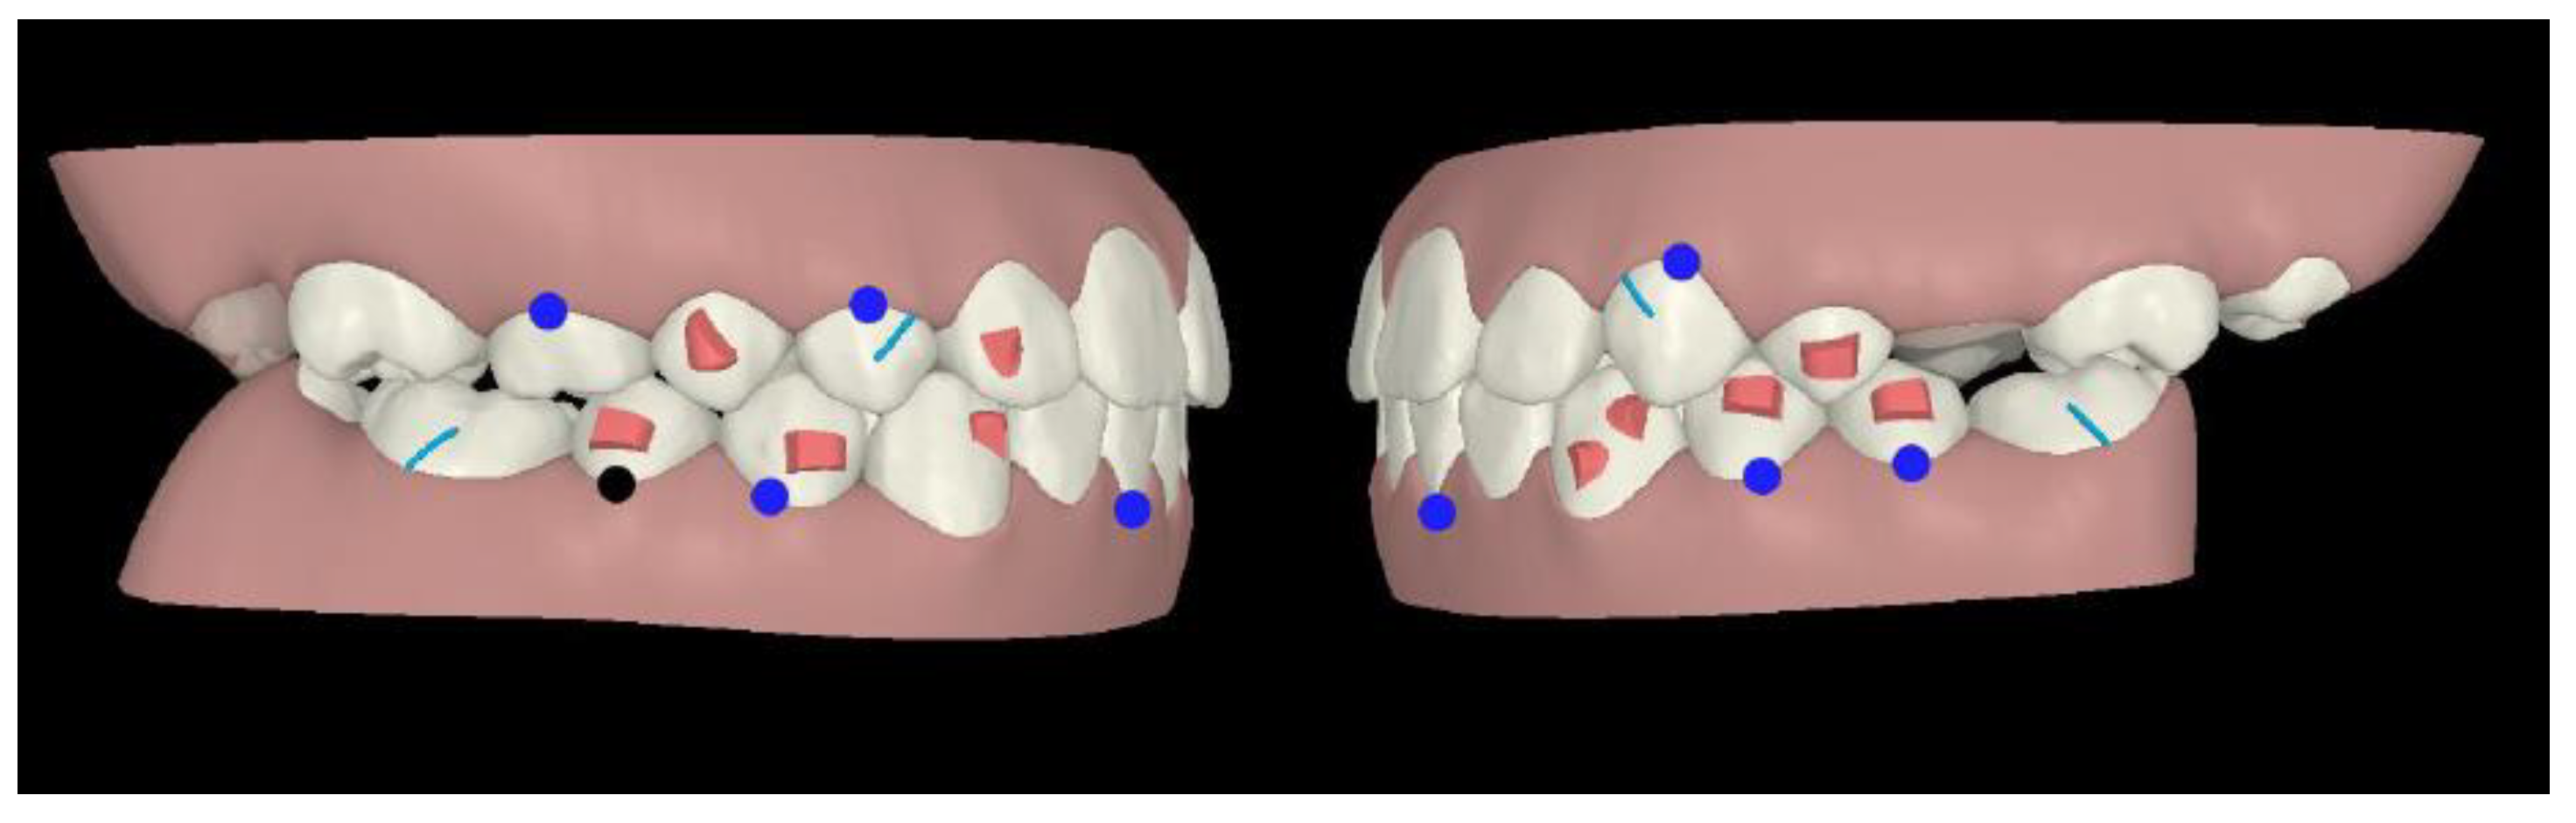

An Invisalign® “Teen” package was chosen, as it allowed to ask for a multi-phase treatment: in fact, it is possible to ask for additional aligners at any stage of tooth eruption. Compliance indicators were provided on the buccal area of the aligners in order to monitor patient’s adherence during treatment. The first phase of treatment was scheduled in late mixed dentition: horizontal attachments were placed over mandibular first and second bicuspids as posterior anchorage to allow intrusion forces of mandibular incisors area, whereas incisors did not require attachments (Figure 2).

Figure 2.

Treatment plan phase I.

On the maxillary right first bicuspid, the optimized rotation attachment was placed for its distal rotation and lingual inclination (Figure 2).

On the maxillary right lateral incisor, an optimized attachment on the labial surface and a pressure point on lingual surface were placed to achieve intrusion and mesial rotation (Figure 2).

On the mandibular left canine, an optimized attachment was planned for root control during its mesial rotation and distal translation, whereas on the mandibular right canine the optimized attachment was placed for its mesial rotation. Moreover, their intrusion was planned (Figure 2).

In first and second phase, precision cuts were designed on the aligner surface for Class II elastics in order to obtain a mandibular advancement (Figure 2 and Figure 3).

Figure 3.

Treatment plan phase II.

The second phase of treatment was scheduled in complete permanent dentition. Rectangular vertical attachments were placed on the maxillary canines for root control and retention for interarch elastics, whereas horizontal attachments over mandibular right bicuspids and second left bicuspid provided anchorage for intrusion of mandibular incisors (Figure 3).

In the second phase, an interproximal reduction of 2 mm was performed on the anterior mandibular arch from first right bicuspid to second left bicuspid (Figure 3).